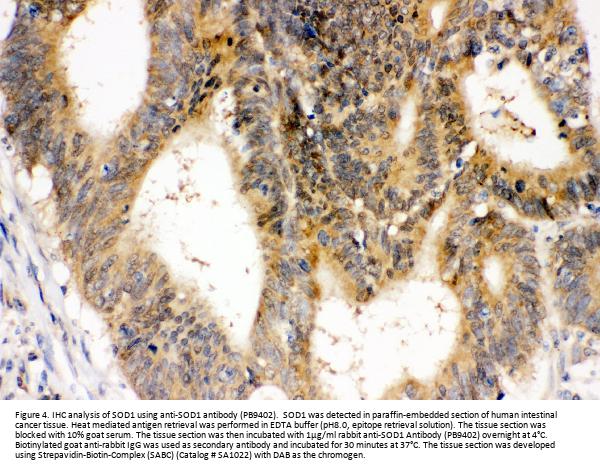

Immunohistochemistry(Paraffin-embedded Section), 2-5 μg/ml, Human

Boster Bio Anti-Superoxide Dismutase 1/SOD1 Antibody Picoband® catalog # PB9402. Tested in Flow Cytometry, IHC, WB applications. This antibody reacts with Human, Mouse, Rat. The brand Picoband indicates this is a premium antibody that guarantees superior quality, high affinity, and strong signals with minimal background in Western blot applications. Only our best-performing antibodies are designated as Picoband, ensuring unmatched performance.